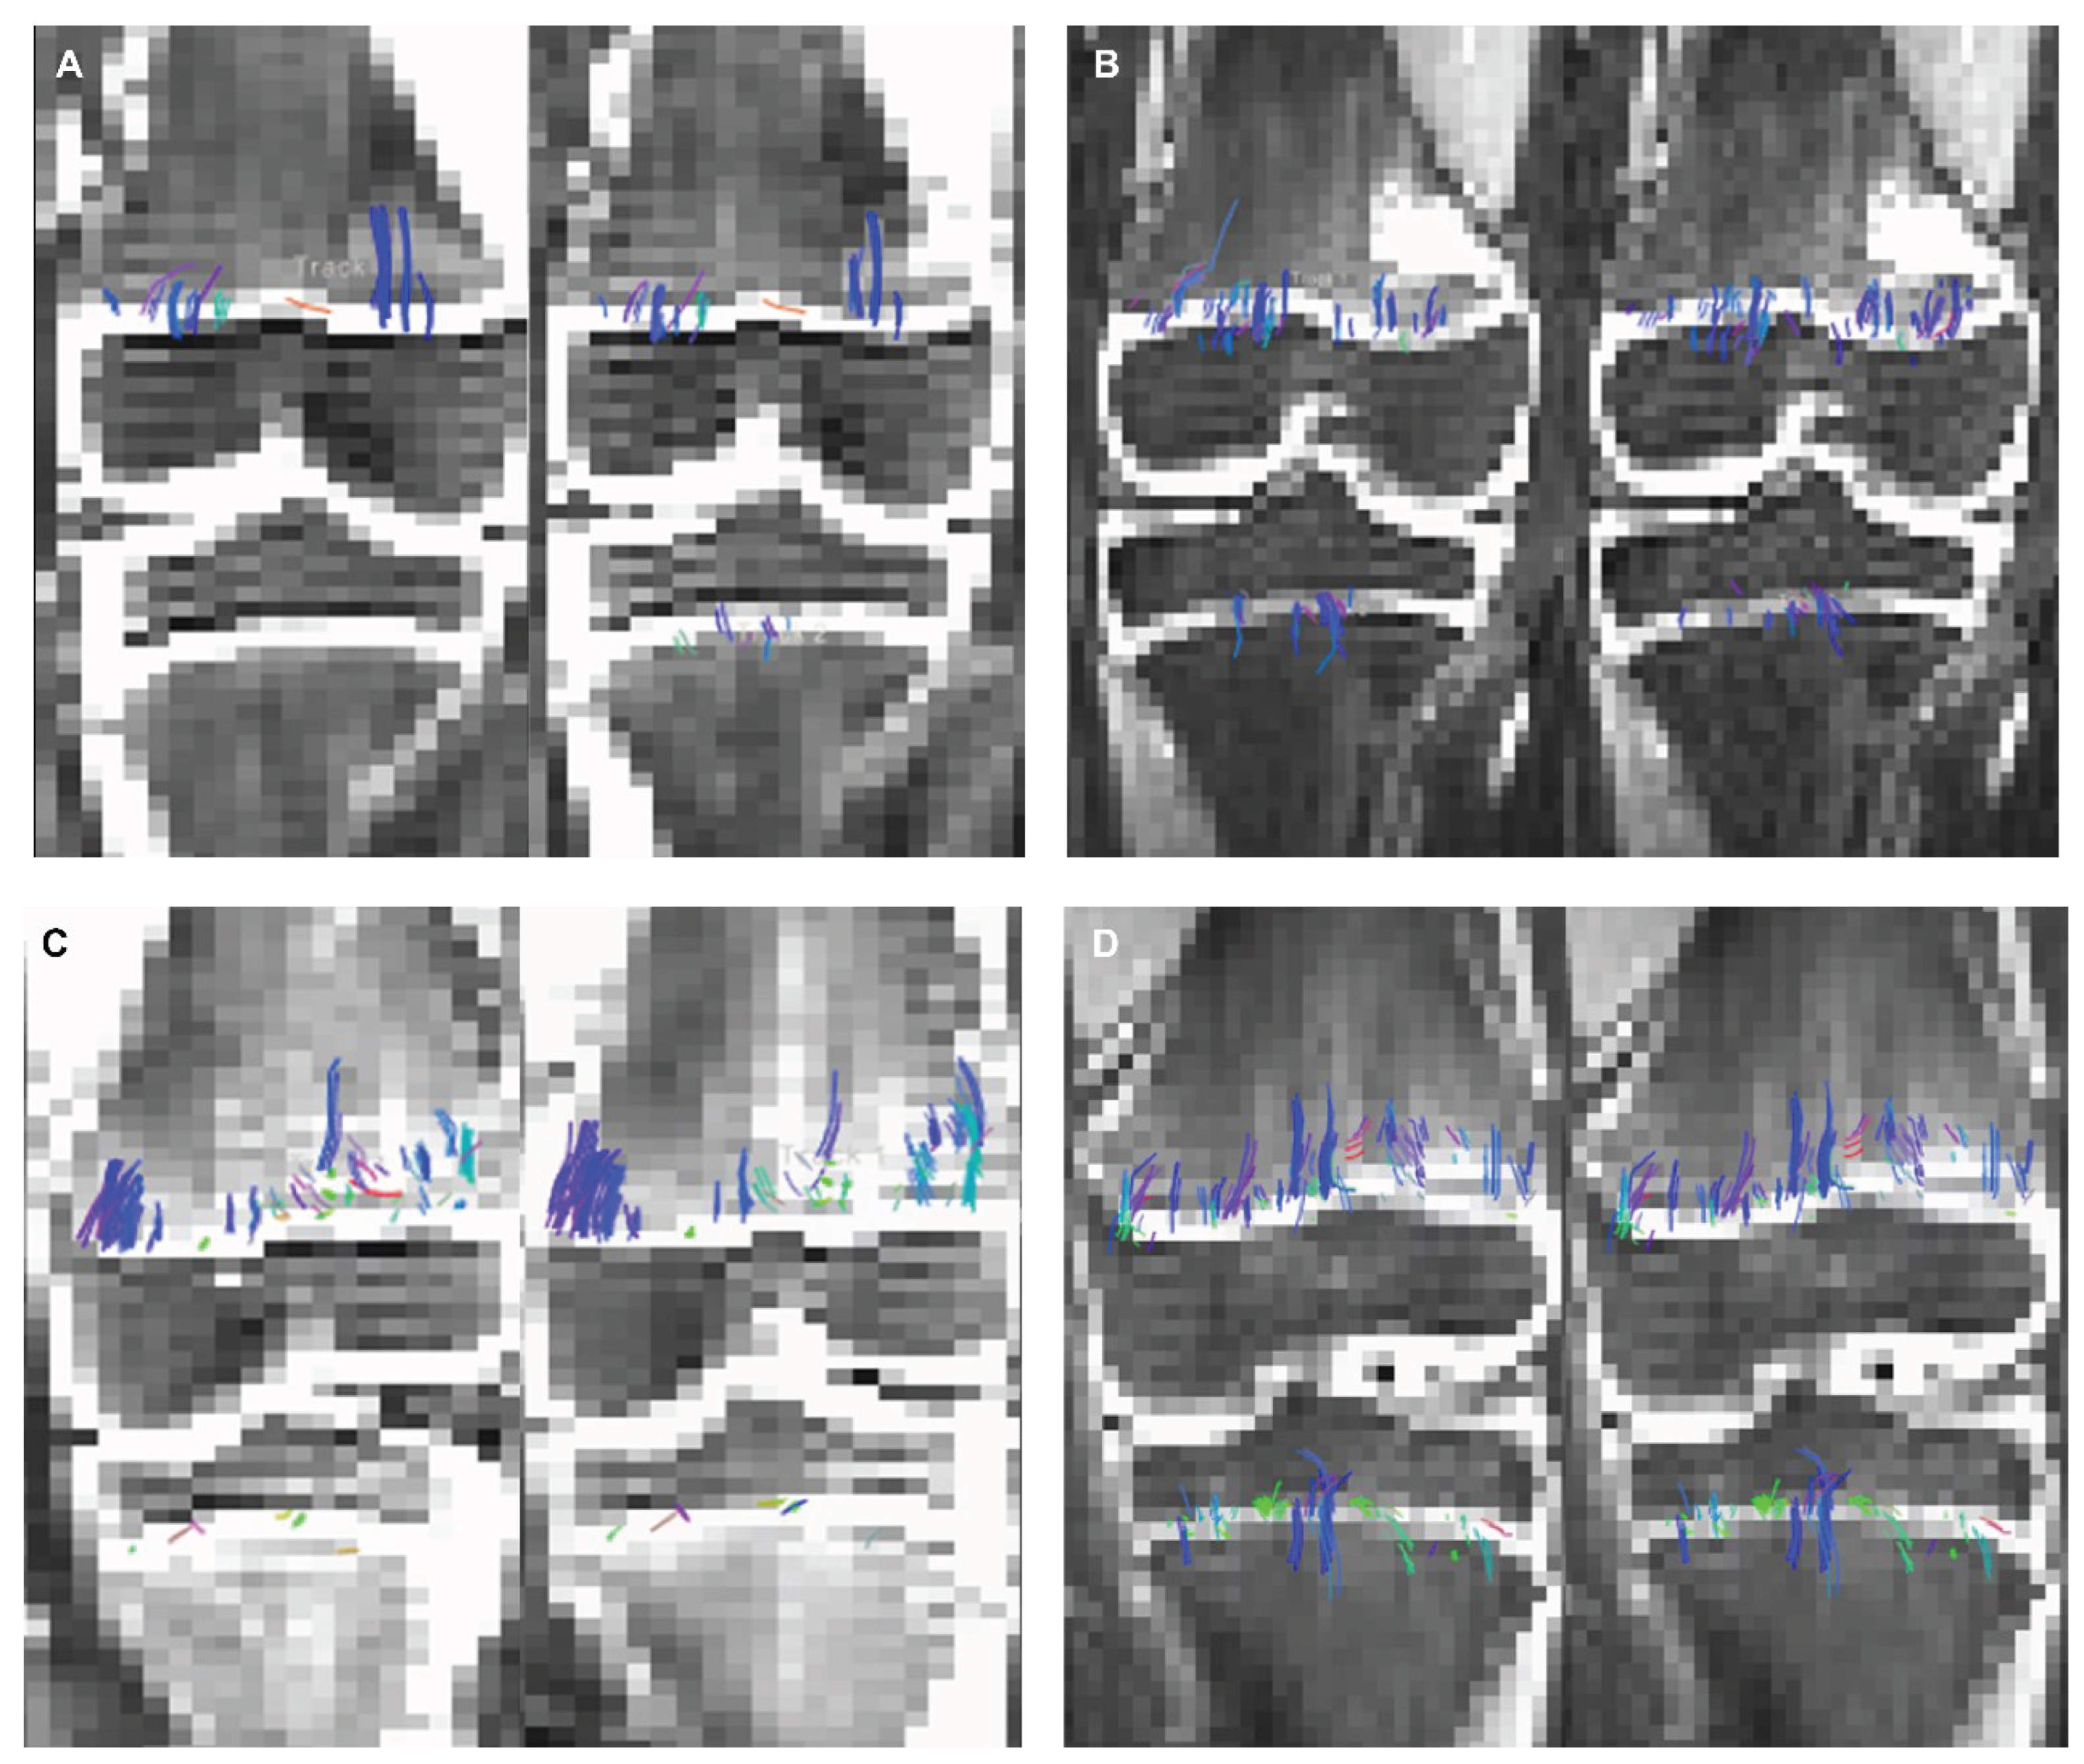

Twenty-seven subjects (14 girls, 13 boys) were included in the study, each subject had 2 DTI sequences to which a DL reconstruction algorithm was applied (n= 27 subjects, n= 54 non-denoised DTI sequences, n= 54 DL reconstructed scans). In all subjects, isovolumetric 2 mm3 DTI scans exhibited a visibly higher quantity of tensor ellipsoids compared to the 2 mm x 2 mm x 3 mm acquisition, a more defined diffusion direction was observed in the smaller voxel size, as shown in Figure 1. Fiber tract count, volume, and length were consistently larger in both the femur and tibia physes when using the isovolumetric 2 mm3 voxel size in both the non-denoised scans and DL reconstructed scans, as shown in Table 1.

Figure 6 (a). 2 mm3 (A) non-denoised (left) and 2 mm3 denoised (right) versus 2 mm x 2mm x 3mm (B) non-denoised (left) and denoised (right) in a 9 year-old female. There is an evident increase in fiber tract on the denoised images acquired with a 2 mm3, while denoised and non-denoised images are very similar using 2 mm x 2mm x 3mm voxel size.

Figure 6 (b). 2 mm3 (C) non-denoised (left) and denoised (right) versus 2 mm x 2mm x 3mm (D) non-denoised (left) and denoised (right) in a10 year-old male. There is an evident increase in fiber tract on the denoised images acquired with a 2 mm3, while denoised and non-denoised images are very similar using 2 mm x 2mm x 3mm voxel size